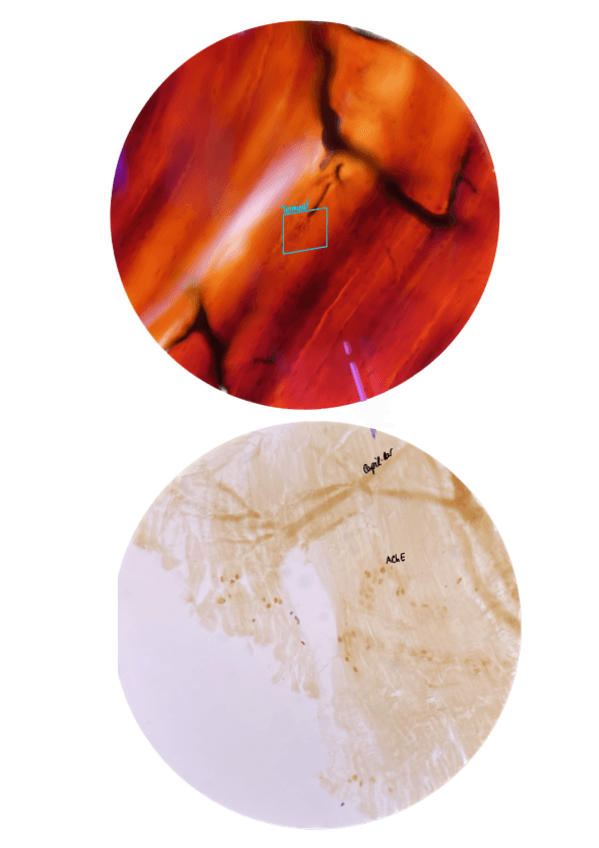

He publicado nuevos practicas de 2º Histología del Sistema Nervioso: Histo-SN-PRACTIQUES-2024-2025.pdf

He publicado nuevos apuntes de 2º Histología del Sistema Nervioso: Practiques-histologia-del-sistema-nervios.pdf

He publicado nuevos practicas de 2º Histología del Sistema Nervioso: Ejemplo-guion-resuelto-practicas-histo-SN.pdf

He publicado nuevos practicas de 2º Histología del Sistema Nervioso: Guio-HSN-22-23-lab.pdf